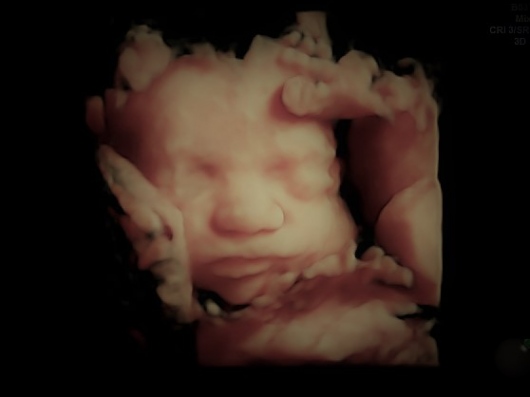

Utilizza correntemente strumenti ecografici all'avanguardia con possibilità di eseguire ecografie 3D e 4D.

• Ecografia 4D

200 €